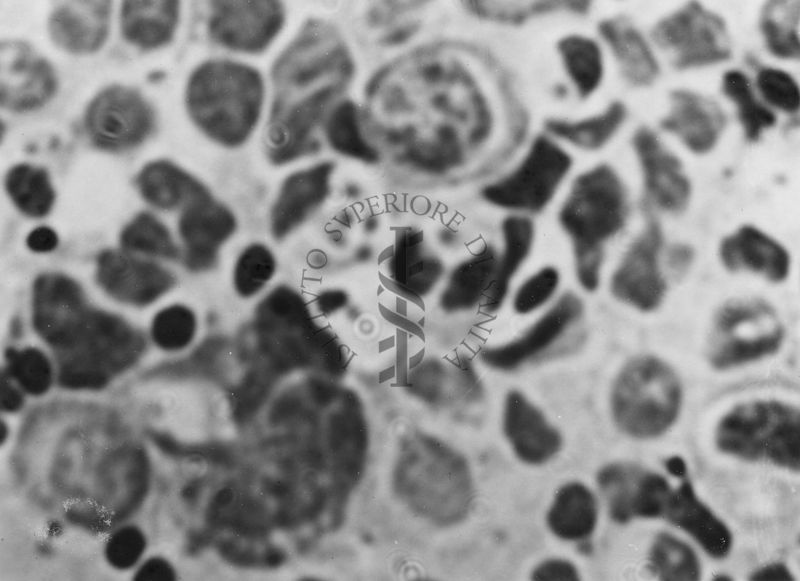

Immagini di Emoprotozoi